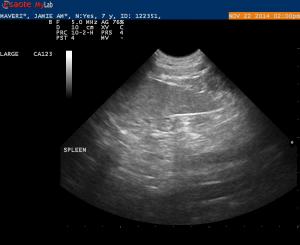

Maverick is a 7 1/2 year old Lab with 2 fairly large cutaneous mast cell tumors.

On x-rays the spleen was prominent but not overly enlarged.

Ultrasound findings were within normal limits. I did not appreciate any lymphadenopathy.

The spleen on first glance appeared to be normal- but when I went back and looked at my images I was wondering if the echotexture was a bit coarse.

1. Do you see any abnormalities with this spleen making it worthwhile to get an aspirate?